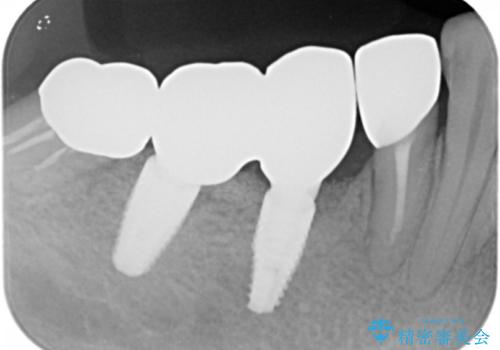

奥歯でしっかり咬むことができるようになり、大変喜んで頂けました。

クラウンの種類:オールセラミッククラウン ベレッツァ